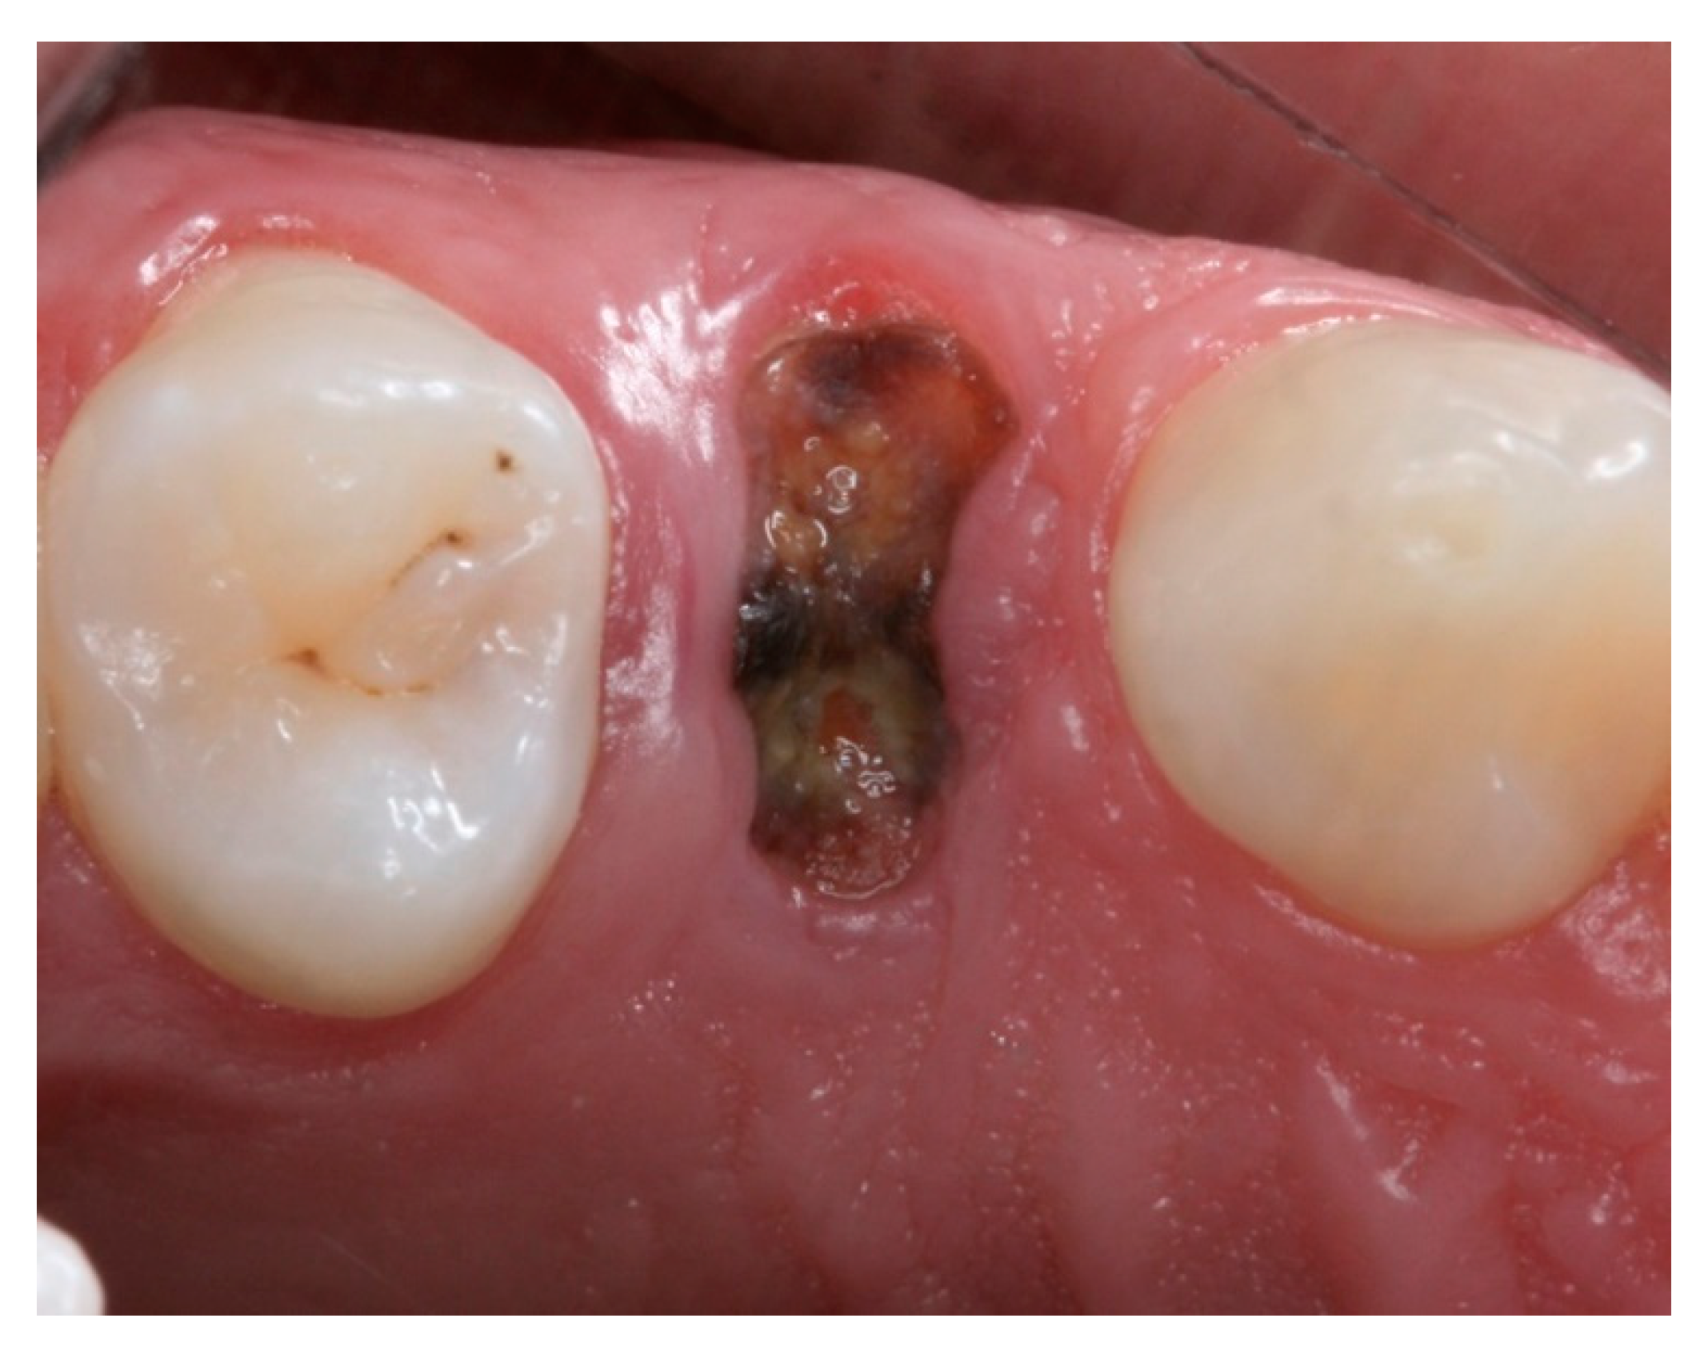

Socket Preservation Using a (Dense) PTFE Barrier with or without Xenograft Material: A Randomized Clinical Trial

2. Materials and Methods

2.4. Groups

2.5. Post-Surgical Procedures